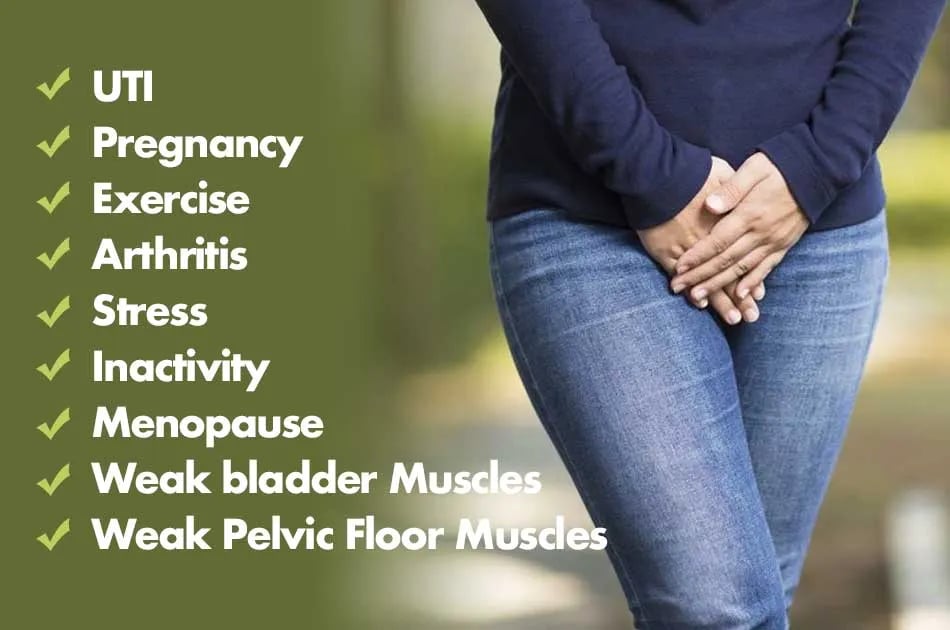

Incontinence Issues?

After my first pregnancy I couldn't laugh or sneeze for a long time without peeing myself…I even had a problem wetting the bed.. and the most inconvenient were my leaks throughout the day at work… sadly nobody knew it but me.

It's called incontinence and it's actually really common for women of all ages and could be caused by any of the following: